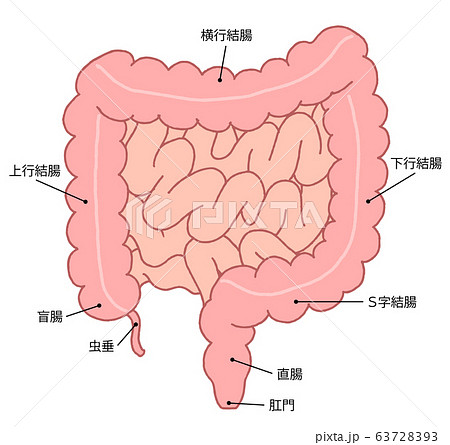

消化器

大腸がんとは 北青山dクリニック

ゆりりこ 結腸 S字結腸 大腸の走行 部位 的に名称を上行 横行 下行 S字 直腸と名称をつけてるだけで全部同じ大腸なのでbl的な結腸まで攻のブツが到達して 何これそんな深いとこまでヤダ 感じる みたいなのはファンタジーだと思います笑 S字から

消化器